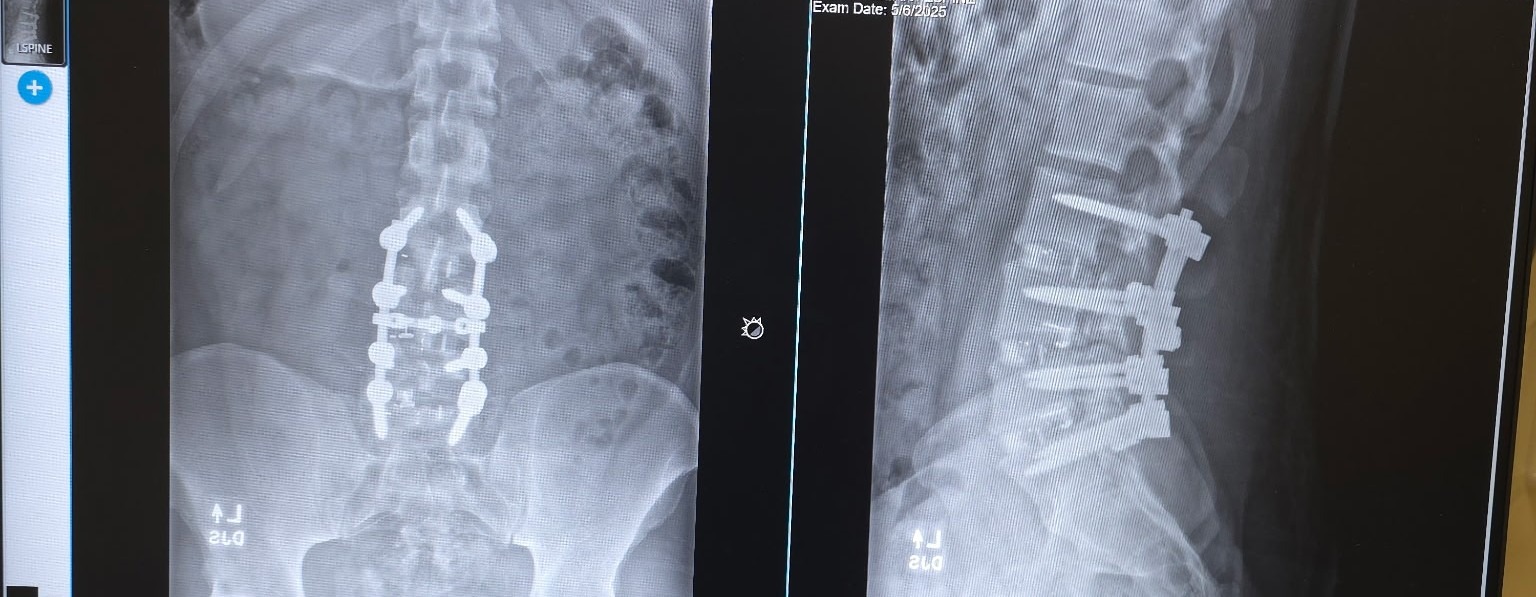

My mother suffers from memory loss and other complications that make everyday life a challenge. My fiancée is dealing with her own medical problems, and I’ve had multiple surgeries on my legs, hips, and spine, plus serious infections and conditions that keep putting me back in the hospital I also have amputations of the feet.